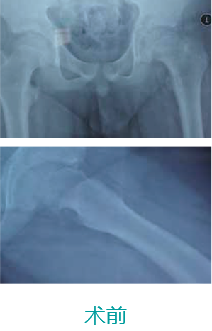

天玑II 辅助小儿股骨颈骨骺滑脱内牢靠术

基本情形:患者男,,,,,,,12岁,,,,,,,跛行一年,,,,,,,加重一周

机械人辅助优势:入钉偏向和骨骺接壤精准定位

病例泉源:北京积水潭医院